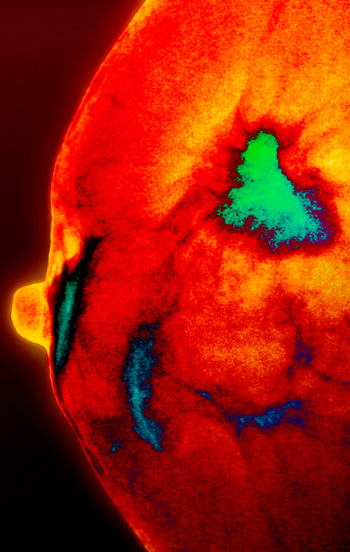

Kolesterolmetabolitten 27-hydroksykolesterol fremmer østrogenreseptoravhengig vekst av humane brystkreftceller.

Forskerne viste at både en kultivert human brystkreftcellelinje, MCF7, og humane brystkreftceller implantert i en musemodell vokste raskere i nærvær av 27-hydroksykolesterol. Kolesterolmetabolitten førte også til raskere spredning av svulsten til andre organer. Undersøkelse av humane brystkreftsvulster viste at de mest aggressive kreftsvulstene inneholdt høyere nivåer av enzymet CYP27A1 (som omdanner kolesterol til 27-hydroksykolesterol) enn de mindre aggressive.